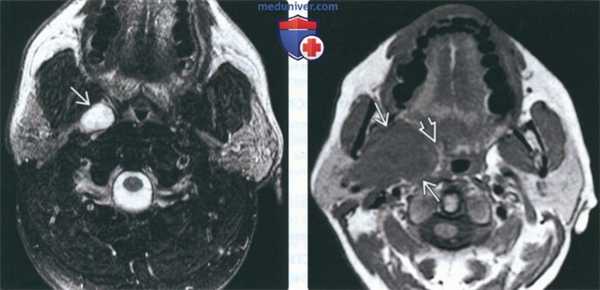

(Слева) На аксиальной МРТ (Т2ВИ FS) во внутреннем околоушном пространстве определяется опухоль овальной формы с неоднородным гиперинтенсивным сигналом. Степень интенсивности сигнала неспецифична для ДСО, такой же сигнал может наблюдаться в других паротидных опухолях.

(Справа) На аксиальной MPT (Т1ВИ) в глубокой доле околоушной железы определяется большая опухоль с промежуточным сигналом. ДСО глубокой доли могут достигать огромных размеров, оставаясь не обнаруженными. Обратите внимание, что окологлоточный жир остается различимым в виде белого полумесяца с внутренней стороны от опухоли.